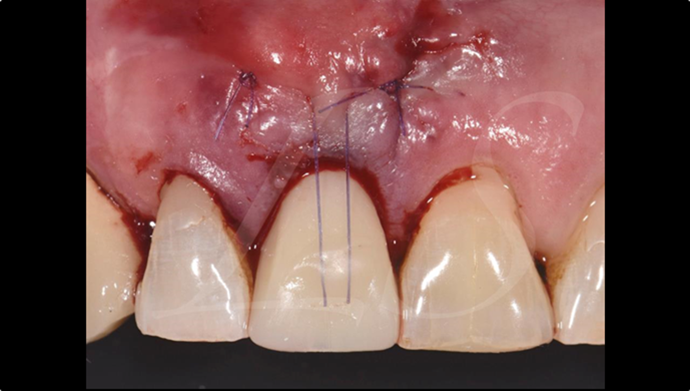

Clinical case: Extraction, immediate placement & loading using

R2GATE solution in aesthetic zone

- Courtesy of Dr. Jong-Cheol Kim, Korea-